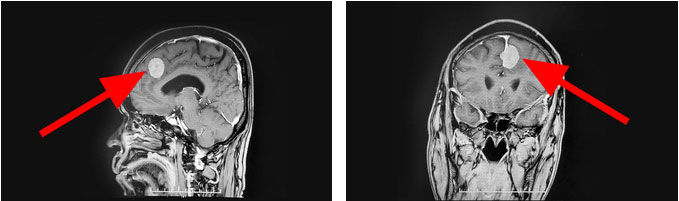

头颅MR显示,患者左侧额部大脑镰旁可见一块团状异常信号影,大小约2.2cm*2.1cm *2.6cm,伴有脑水肿。由神经外科6B病区主任潘仁龙、李士其教授、吴治群博士组成的专家组会诊后指出,患者颅内占位明确,根据影像学表现考虑为左侧额部大脑镰旁脑膜瘤。肿瘤的体积较大,相邻脑组织受压明显,应尽早接受手术治疗。

▲ 肿瘤位于左侧额部大脑镰旁